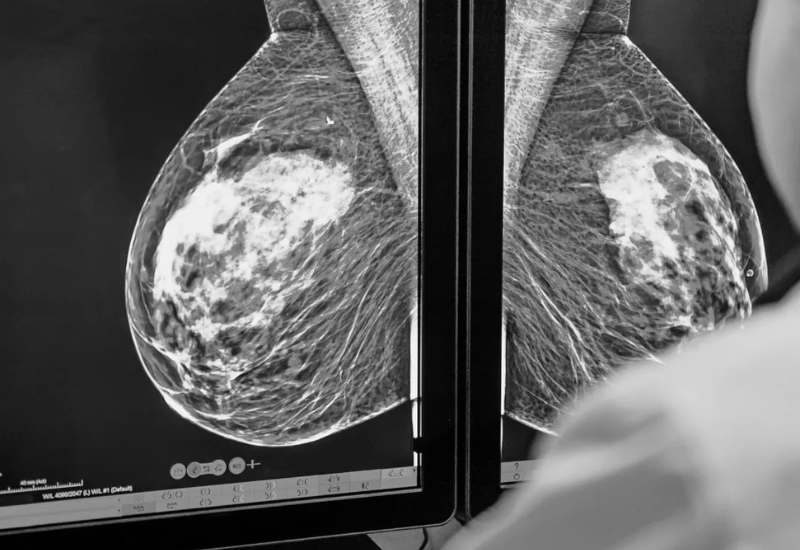

Chụp nhũ ảnh là kỹ thuật hình ảnh sử dụng tia X để thu được những bức ảnh chi tiết của tuyến vú. Phương pháp này có khả năng phát hiện những bất thường nhỏ, các tổn thương, khối u hay dấu hiệu vi vôi hóa mà thăm khám thông thường khó có thể nhận thấy. Đây được xem là một dạng X-quang chuyên biệt cho tuyến vú, giữ vai trò quan trọng trong việc sàng lọc và chẩn đoán ung thư vú.

Chụp nhũ ảnh là kỹ thuật hình ảnh có khả năng phát hiện những bất thường tại tuyến vú